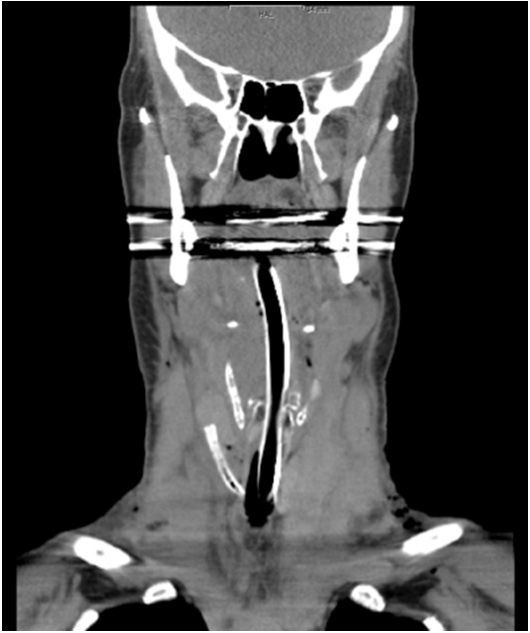

Figure 2: Postoperative CT-scan: Larynx, hypopharynx and parts of the oropharynx heavily edematous. Lumen of trachea in the neck area just kept braced by the tubus.

figure 2